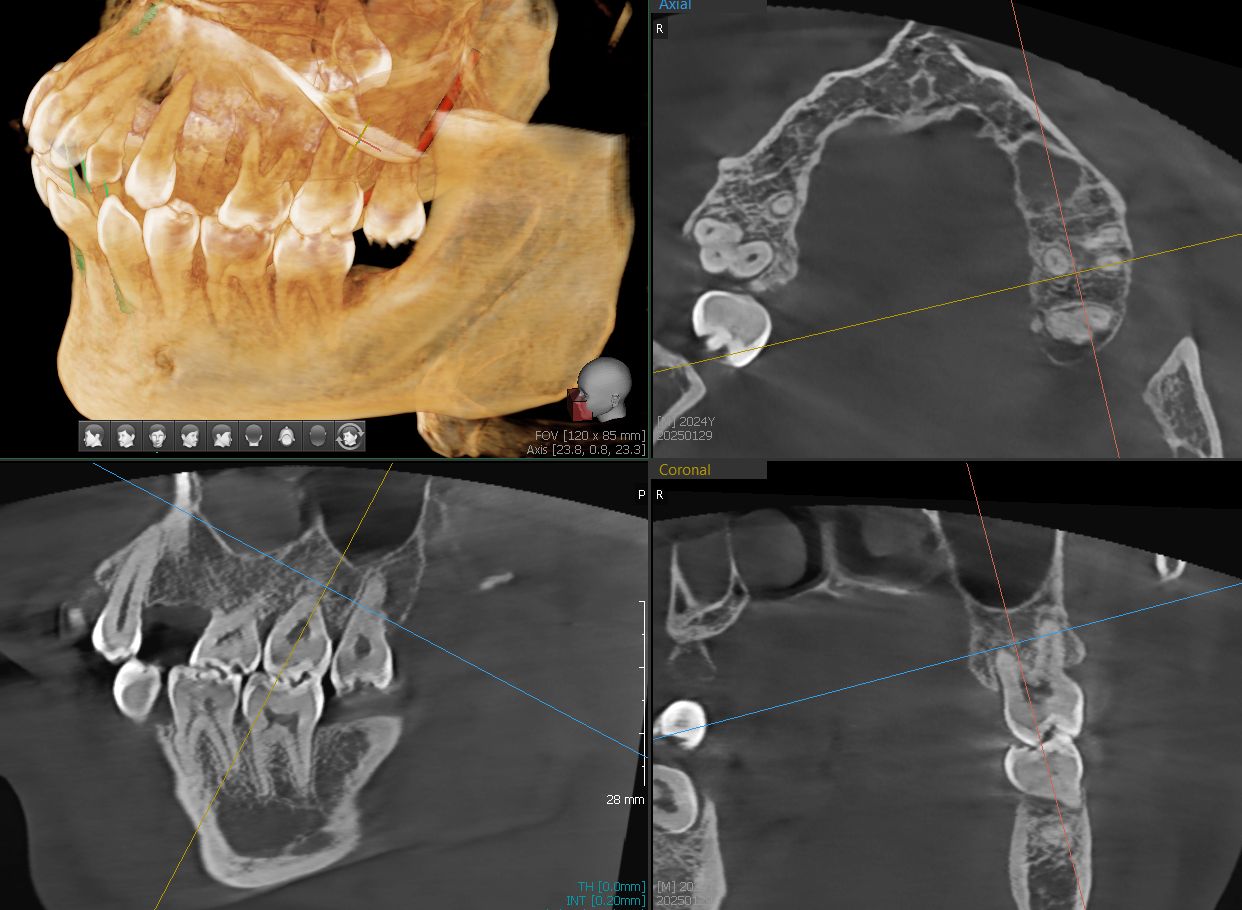

Diagnosing Periodontal Disease:

Traditionally, periodontal probing was used to assess bone loss. At Boston Finesse Dentistry & Implant Center , we utilize advanced CBCT (Cone Beam Computed Tomography) technology, providing a detailed, three-dimensional view of bone levels for precise diagnosis and treatment.